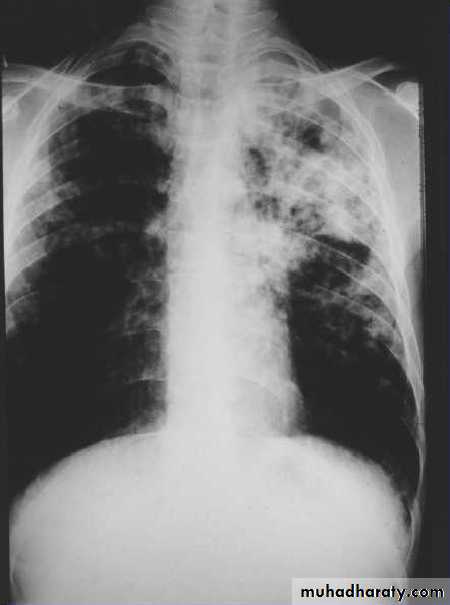

Figure 1. Pulmonary tuberculosis in a 48 year old man. Soft shadowing is shown in both upper lobes with cavitation on the right. This picture is characteristic of tuberculosis in an HIV negative person.

The characteristic shadowing of post primary tuberculosis can make the diagnosis of tuberculosis appear easy. The shadowing is soft, fluffy, predominantly in the upper lobes, and often with cavitation.

But pulmonary tuberculosis can present with virtually any radiographic pattern (especially in the presence of HIV infection). So a chest x ray cannot definitively confirm the diagnosis of tuberculosis.